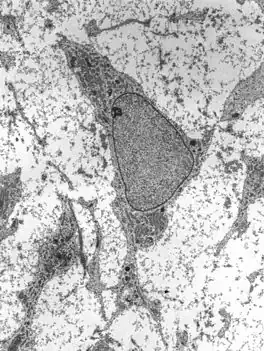

![]() Transmission electron micrograph of a mesenchymal stem cell displaying typical ultrastructural characteristics | |

Mesenchymal stem cells (MSC) or mesenchymal stromal cells, also known as medicinal signaling cells are known to be multipotent, which can be found in adult tissues, for example, in the muscle, liver, bone marrow and adipose tissue. Mesenchymal stem cells usually function as structural support in various organs as mentioned above, and control the movement of substances. MSC can differentiate into numerous cell categories as an illustration of adipocytes, osteocytes, and chondrocytes, derived by the mesodermal layer.[34] Where the mesoderm layer provides an increase to the body's skeletal elements, such as relating to the cartilage or bone. The term "meso" means middle, infusion originated from the Greek, signifying that mesenchymal cells are able to range and travel in early embryonic growth among the ectodermal and endodermal layers. This mechanism helps with space-filling thus, key for repairing wounds in adult organisms that have to do with mesenchymal cells in the dermis (skin), bone, or muscle.[35]

Mesenchymal stem cells are known to be essential for regenerative medicine. They are broadly studied in clinical trials. Since they are easily isolated and obtain high yield, high plasticity, which makes able to facilitate inflammation and encourage cell growth, cell differentiation, and restoring tissue derived from immunomodulation and immunosuppression. MSC comes from the bone marrow, which requires an aggressive procedure when it comes to isolating the quantity and quality of the isolated cell, and it varies by how old the donor. When comparing the rates of MSC in the bone marrow aspirates and bone marrow stroma, the aspirates tend to have lower rates of MSC than the stroma. MSC are known to be heterogeneous, and they express a high level of pluripotent markers when compared to other types of stem cells, such as embryonic stem cells.[34] MSCs injection leads to wound healing primarily through stimulation of angiogenesis.[36]